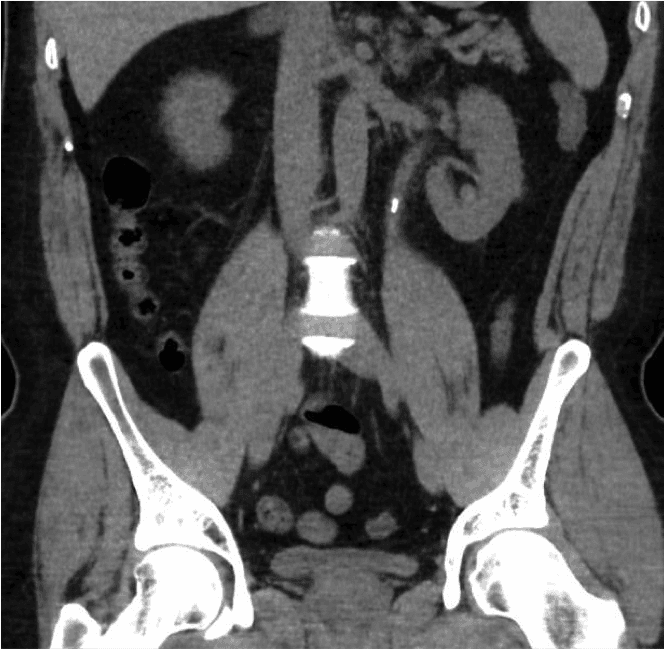

शुरुआत में पेशाब में खून की जाँच और मूत्र संक्रमण की संभावना का पता लगाने के लिए यूरिन डिपस्टिक टेस्ट किया जाएगा। गुर्दे की कार्यप्रणाली और कैल्शियम की जाँच के लिए रक्त परीक्षण भी किए जाएँगे। पथरी का निश्चित निदान पेट का सामान्य सीटी स्कैन (सीटी किडनी यूरेटर ब्लैडर एरिया या सीटी केयूबी) है। इससे पथरी का आकार और स्थिति का पता चलेगा जिससे उपचार की योजना बनाने में मदद मिलेगी।